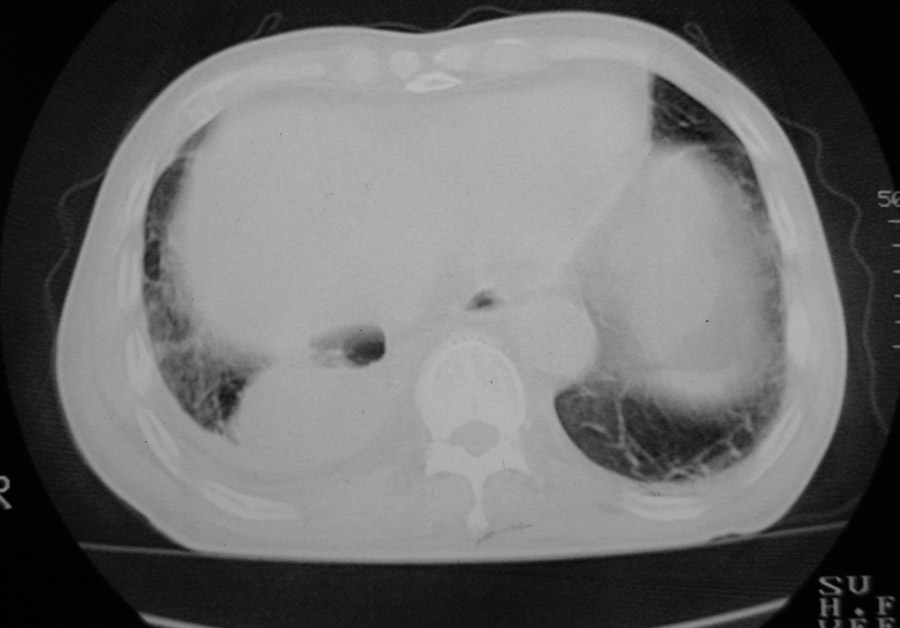

以下是引用hhcckk在2007-1-24 18:11:00的发言:[br]病灶周围胸膜反应比较明显,考虑炎症可能性大点,病人年龄较大,病灶成块状,肿瘤也不能排除,可可西里老师看片子的确很仔细,隔离肺暂时我觉得证据的说服力不大,上下层面显示条状影范围较长,可能是增厚的胸膜,可以做个增强鉴别一下